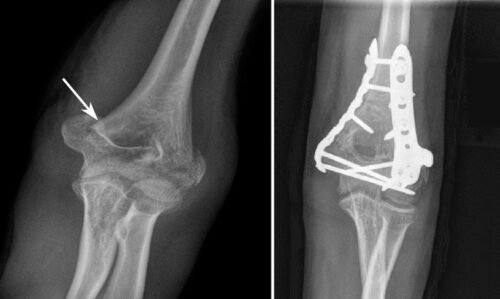

تثبيت الكسور بالشرائح والمسامير

ومع تقدم العلم اختلفت أنواع تثبيت الكسور جراحيًا تبعًا لنوع الكسر ومكانه ، وأيضًا تبعًا لعمر المريض وضمن هذه الأنواع هي تركيب الشرائح والمسامير الطبية، وتركيب المثبتات الخارجية والمسامير النخاعية ويحتاج الطبيب المعالج لعمل بعض الأشعات اللازمة لتحديد النوع المناسب لتثبيت الكسور.

ويقوم الطبيب بتثبيت الكسور والشروخ في جسم الإنسان بواسطة تركيب شرائح طبية ومسامير تساعد على التئام الكسر بشكل طبيعي وفي مكانه الصحيح مما يضمن للمريض استعادة حياته اليومية بشكل سريع وبدون ألم. وتناسب هذه الشرائح والمسامير بصفة خاصة الكسور القريبة من المفاصل.

كيف تتم عملية تركيب الشرائح والمسامير؟

- بعدها يقوم طبيب العظام بعمل شق جراحي يتناسب مع السطح الخارجي للجلد ثم يتعمق إلى الداخل إلى أن يصل إلى موضع العظام المكسورة.

- بعدها يقوم طبيب العظام بتنظيف وتعقيم الجرح بشكل جيد والمنطقة المحيطة به يليها استخدام الشرائح والمسامير على حسب ما يتناسب مع الكسر.

- بعدما ينتهي الطبيب من تثبيت العظام المكسورة من الداخل حتى يبدأ في تعقيم الجرح جيداً ومن ثم تضميد الجرح من الداخل في الأول ومن ثم يصل إلى السطح الخارجي للجلد، حيث يقوم بتضميده بشكل خاص من أجل أن لا يكون ظاهر وواضح بقدر الإمكان.